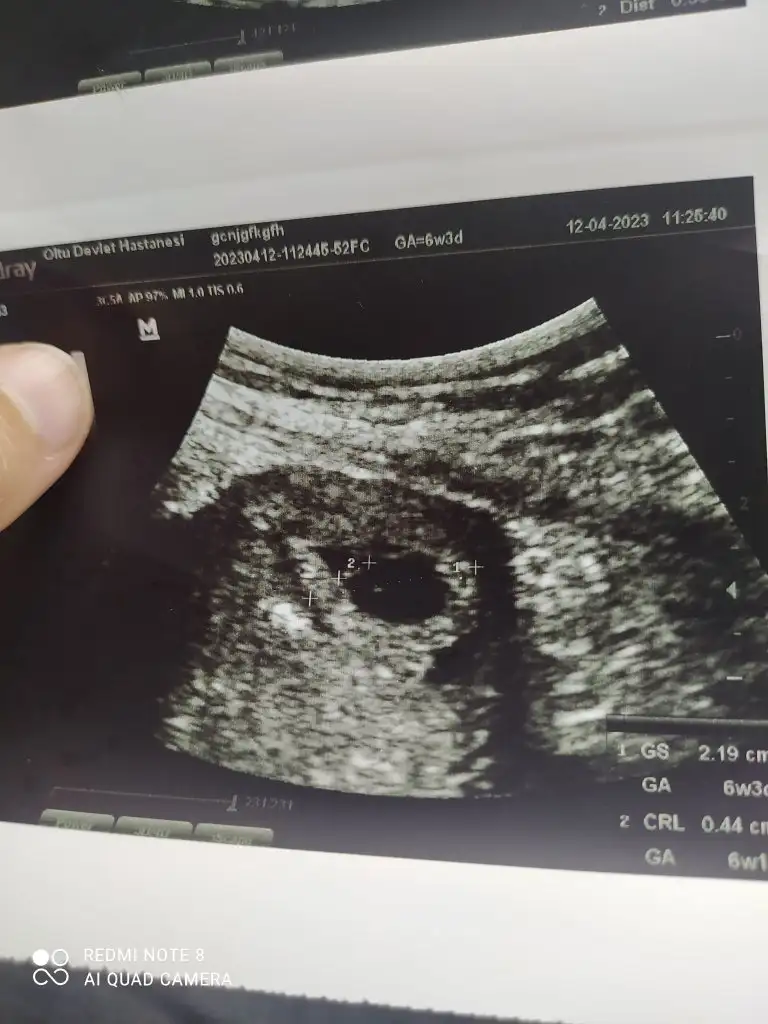

Evet kadın doğum doktoru baktı canım , damar genişlemesi olabilir. Belki bir yara vardı o kanama yapmış olabilir , Corasprin kaynaklı olabilir , üstüne görme olabilir dedi, ama alanda hiç bir kanama görmedi hatta bebişin gelişimi de 3gün ilerde imiş .